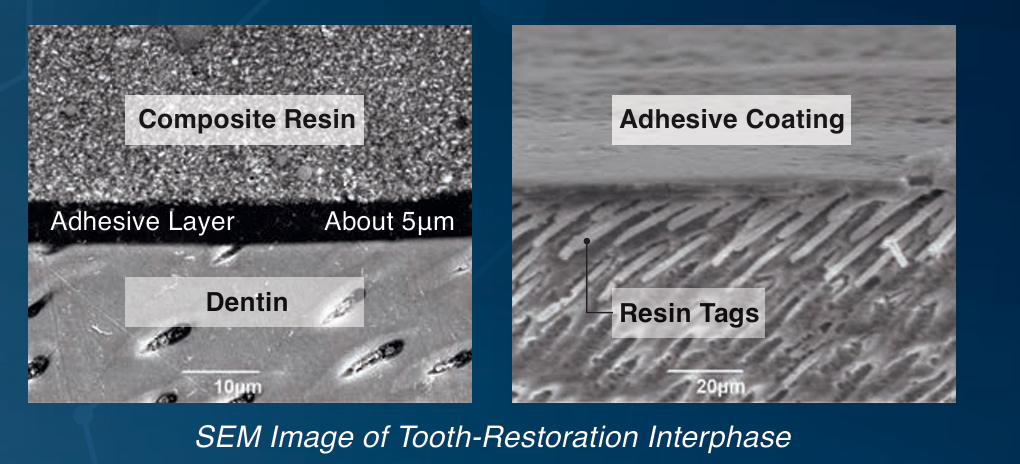

- Provides a thin, uniform layer (5µm).

- Penetrates deep into dentinal tubules for secure adhesion.

- Eliminates postoperative sensitivity and microleakage.

- Extremely low film thickness (5µm).

Preventing Sensitivity and Marginal Adaptation

- Illustrates how BeautiBond Xtreme seals dentinal tubules, preventing sensitivity.

- Provides SEM images showing the adhesive coating and sealed layer.

- Showcase SEM Image of Tooth-Restoration Interphase.

- predictable adhesion with a thin and uniform bonding layer of 5 microns.

- Creating secure interlocking network, eliminating the risk of post-op sensitivity and protecting against microleakage.

It provides an optimal seal to wet or dry dentin, penetrating deep into the dentinal tubules to create resin tags.

It has an extremely low film thickness of 5µm.